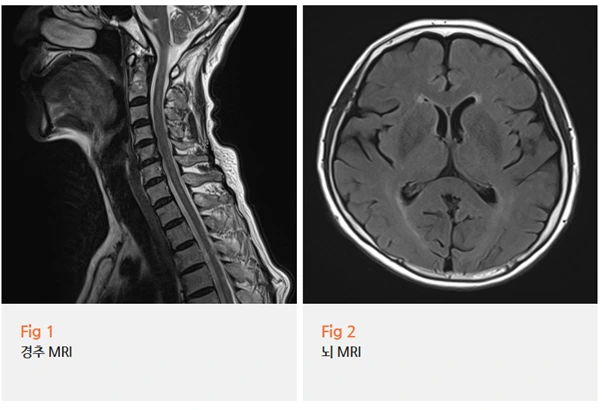

저는 진찰 후 당일 경추 MRI와 뇌 MRI를 모두 촬영하자고 했어요.

검사 결과가 나왔을 때 예상이 맞았어요.

경추 MRI에서 C5, C6, C7번 디스크 팽윤 소견이 확인됐고,

뇌 MRI에서는 다른 뇌 병변은 없었어요.

신경과와 협진으로 뇌 원인을 배제하고 나서,

목에서 내려오는 신경 압박이 어지럼증과 두통, 불면까지 유발하고 있다는 결론에 도달했죠.

경추성 어지럼증이라고 부르는 상태였어요.